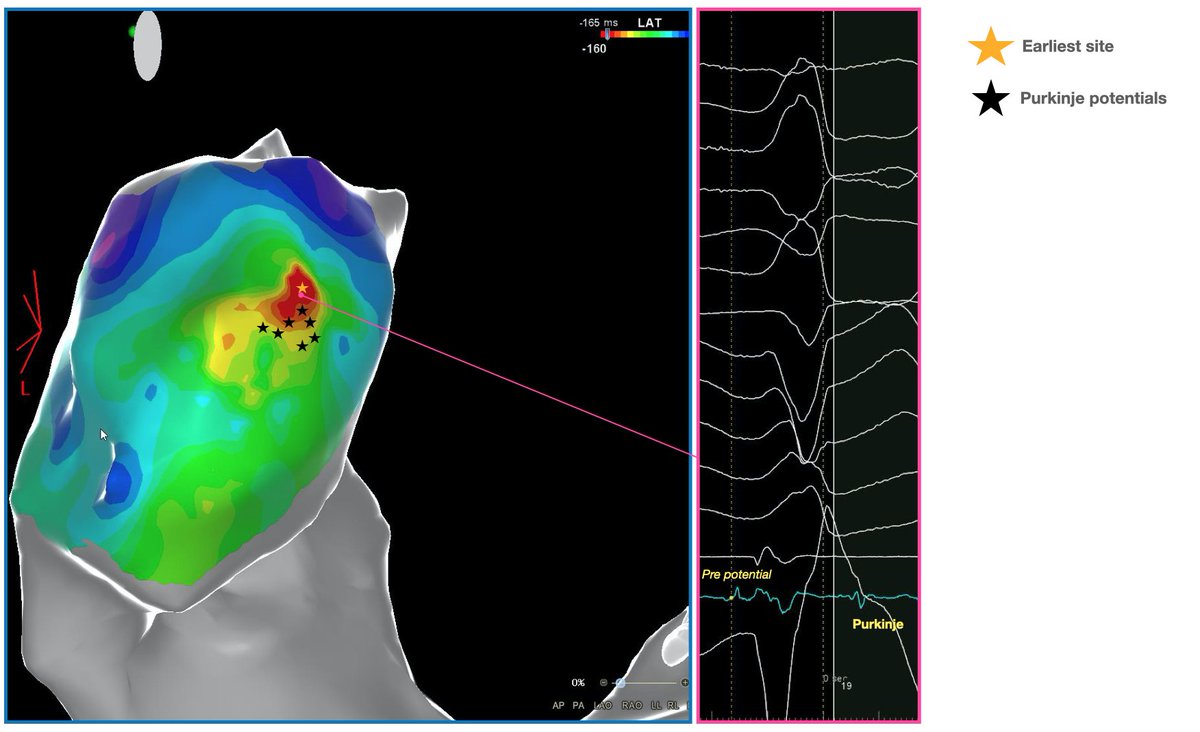

27yo girl. High burden PVCs with NSVT at the last holter 24h ECG. In these cases, purkinje potentials must be searched at the RVOT site. Precise timing of Purkinje potentials were crucial for triggering doublets or triplets. #Porn in #Electrophysiology.